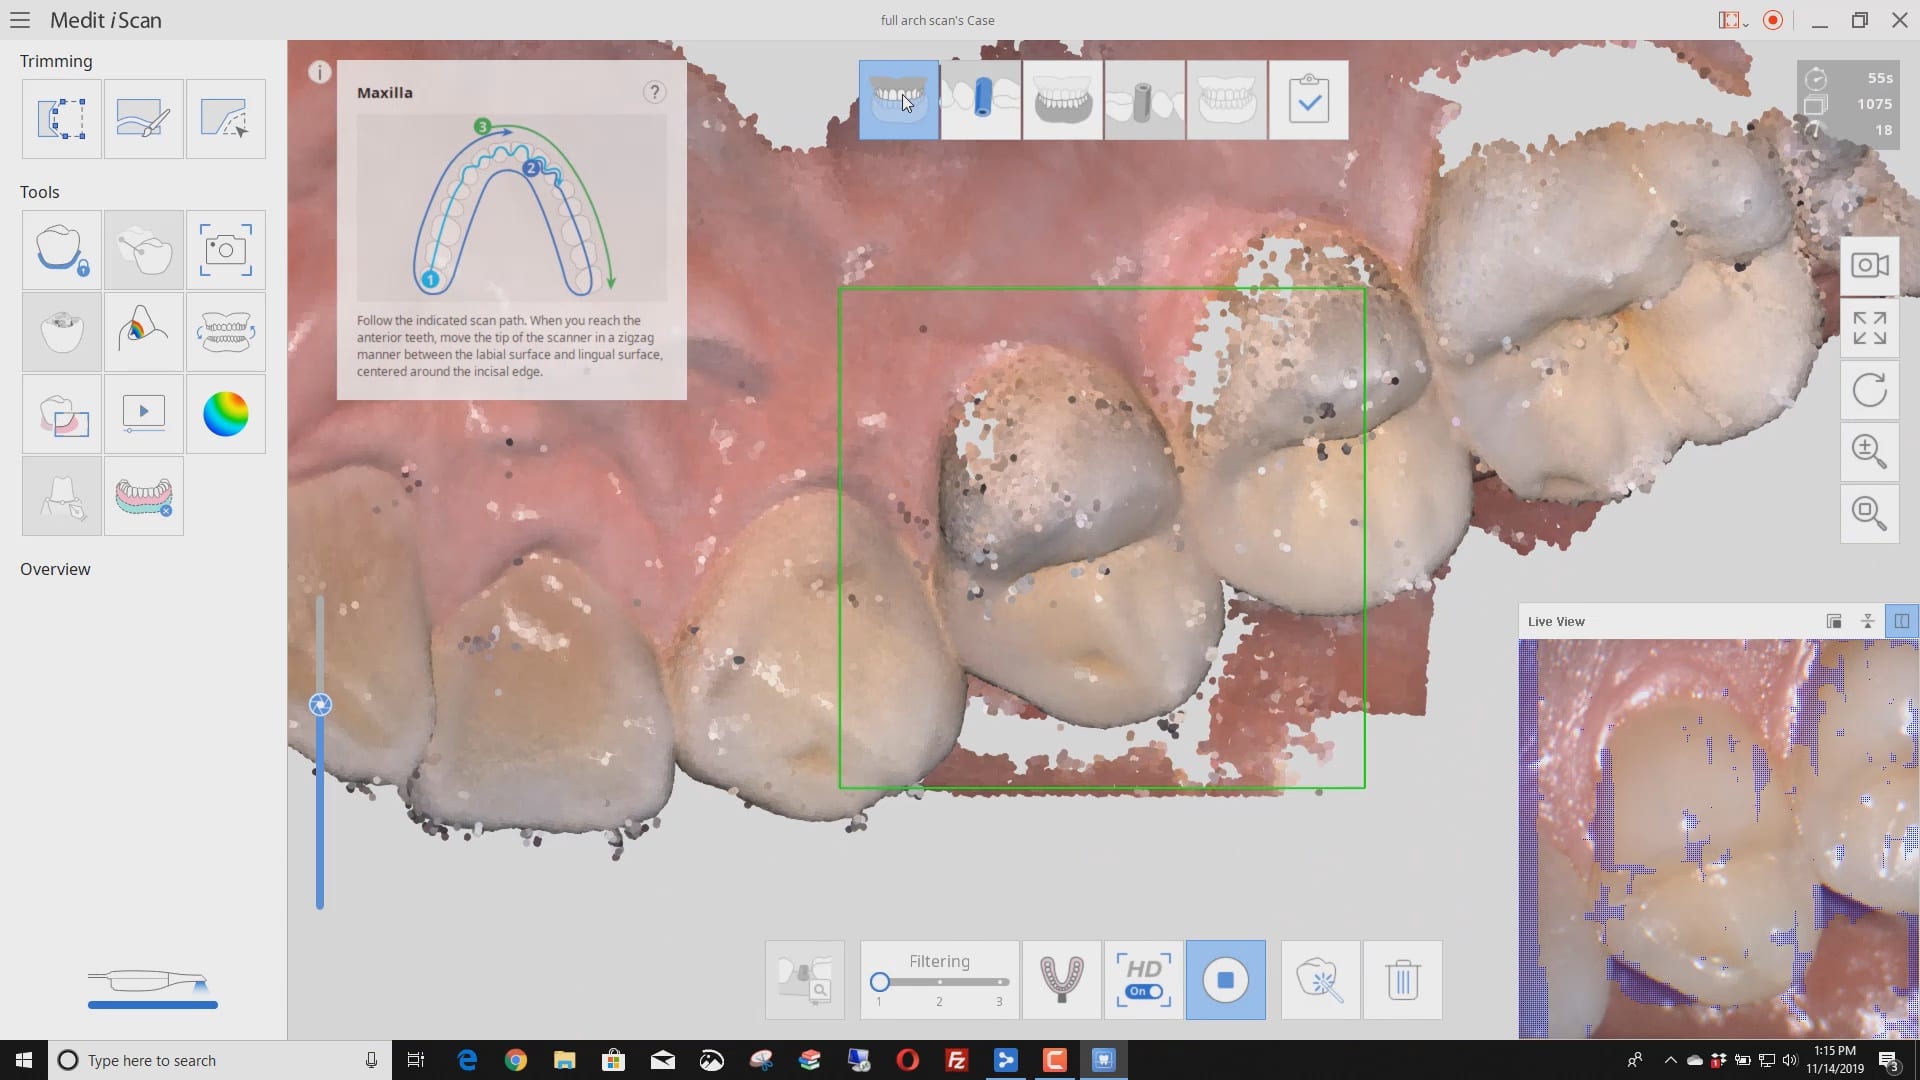

November 19, 2019Have you ever compared the milled product with the designed restoration? We scanned with the medit i500, designed with exocad and milled with coritec. after try-in, we scanned the restoration […]